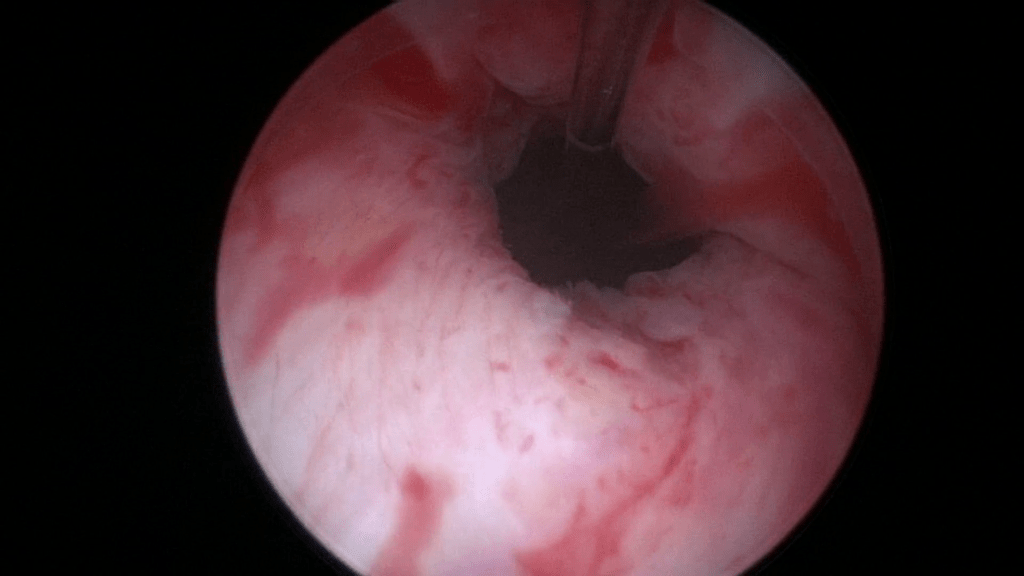

Rotate the sheath and inject now at the 3 o’clock position. Again notice that the bevel of the needle faces the center of the lumen and that an adequate “mucosal shelf” is formed.

Image after injecting the second 0.5ml of Bulkamid® hydrogel at the 3 o’clock position.

The needle is shortly removed and the second syringe of 1ml Bulkamid® hydrogel is loaded. Find the exact location of the previous injections and continue with the next one at 9 o’clock.

Image after injecting the third 0.5ml Bulkamid® hydrogel at 9 o’clock.